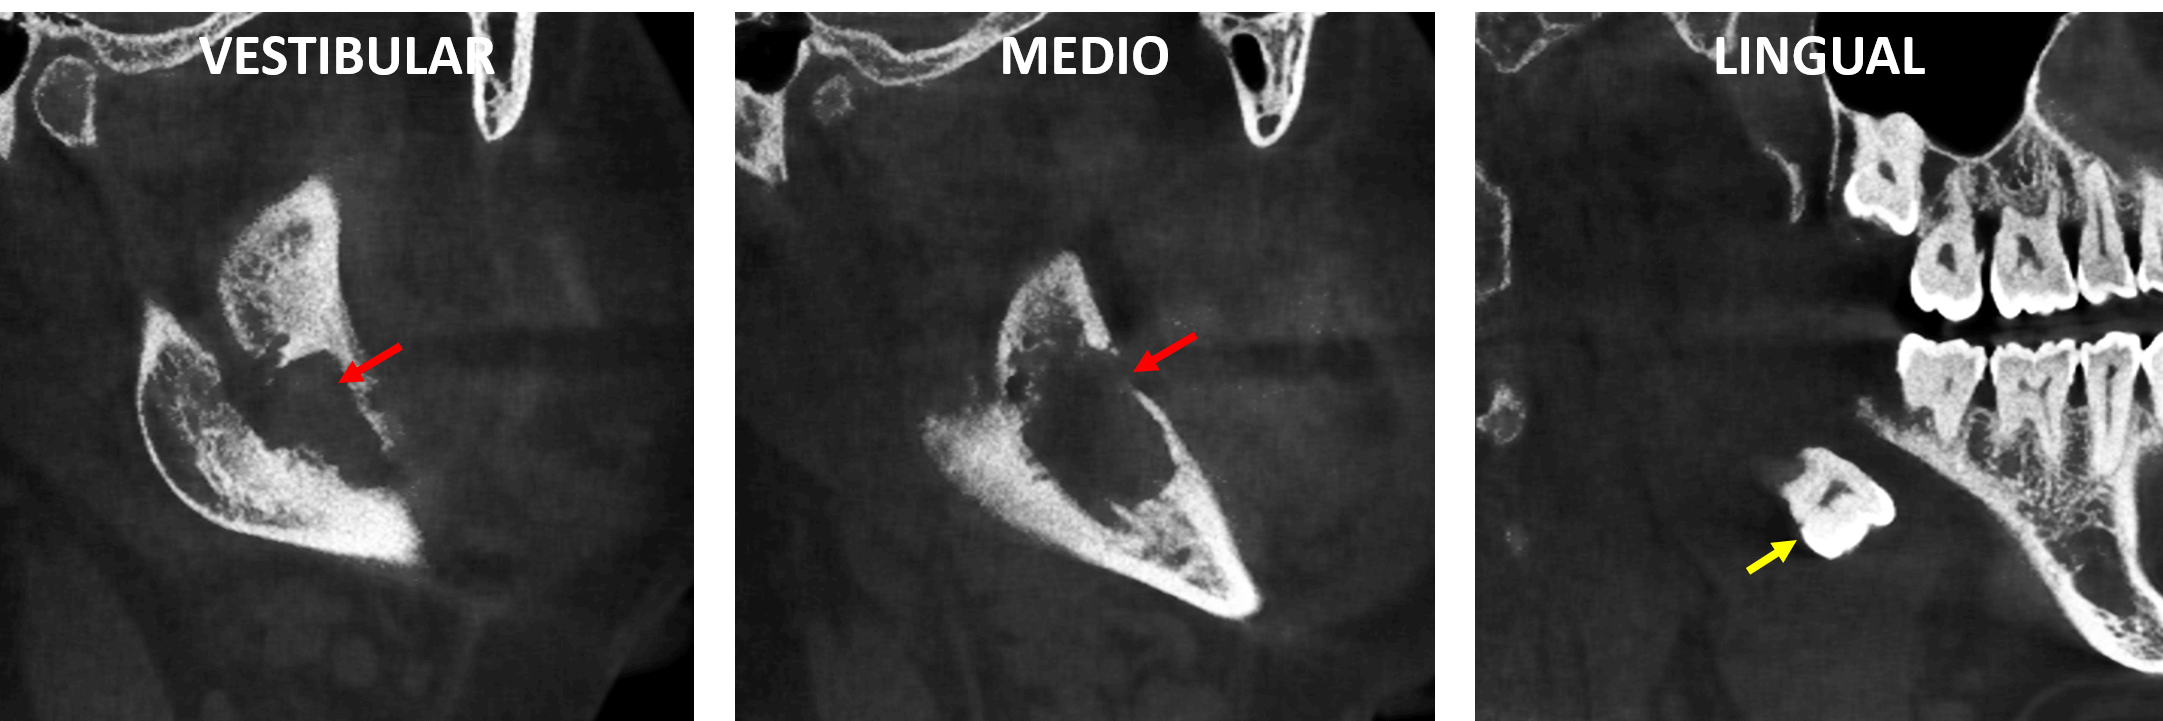

En cortes sagitales (Fig.4) se observa el defecto óseo amplio que compromete también la cortical del reborde alveolar a nivel de la zona retromolar (corte medio) y la presencia del órgano dentario 38 localizado en el tejido blando por lingual.